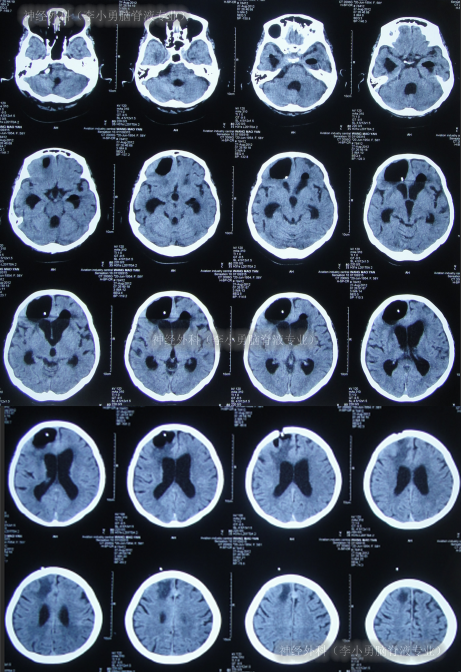

但2012年6月13日(第5家医院治疗22天)凌晨3点患者突发昏迷,体温39.6℃,测血压130/90mmHg,查头颅CT(图-10)后给予甘露醇、退热药物治疗后,体温可逐渐下降,但意识仍不见好转(家属叙述当时抢救了一天一宿)。

图-10:2012年6月13日头颅CT

2012年6月14日(第5家医院治疗23天),家属上午找到李小勇主任看过片子后确定可以接收,于是当天急诊转入李小勇脑脊液专业。